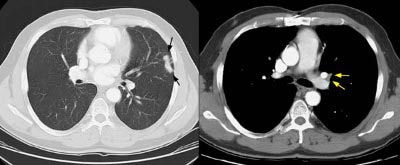

Example 2: This patient is an example of a false negative CT for hilar nodal metastases even when applying the suggested new criterion. The patient had a peripheral adenocarcinoma in the left upper lobe (black arrows). The left hilar node (yellow arrows) is not pathologic by size criteria, nor does it exhibit a convex margin with the adjacent lung parenchyma. This is a normal node by CT, however, at histopathologic analysis the node was positive for malignant cells.

NOTE:  Click image to enlarge